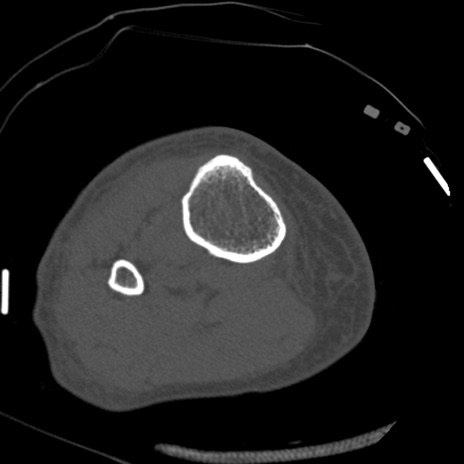

症例28 右膝関節CT(横断像)

右膝関節CT